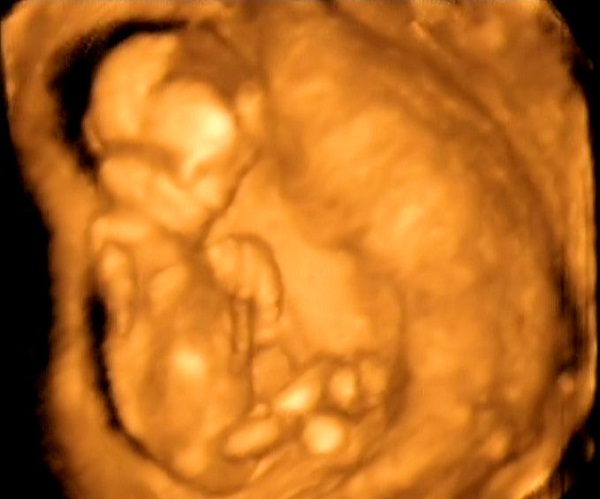

Manócskánk